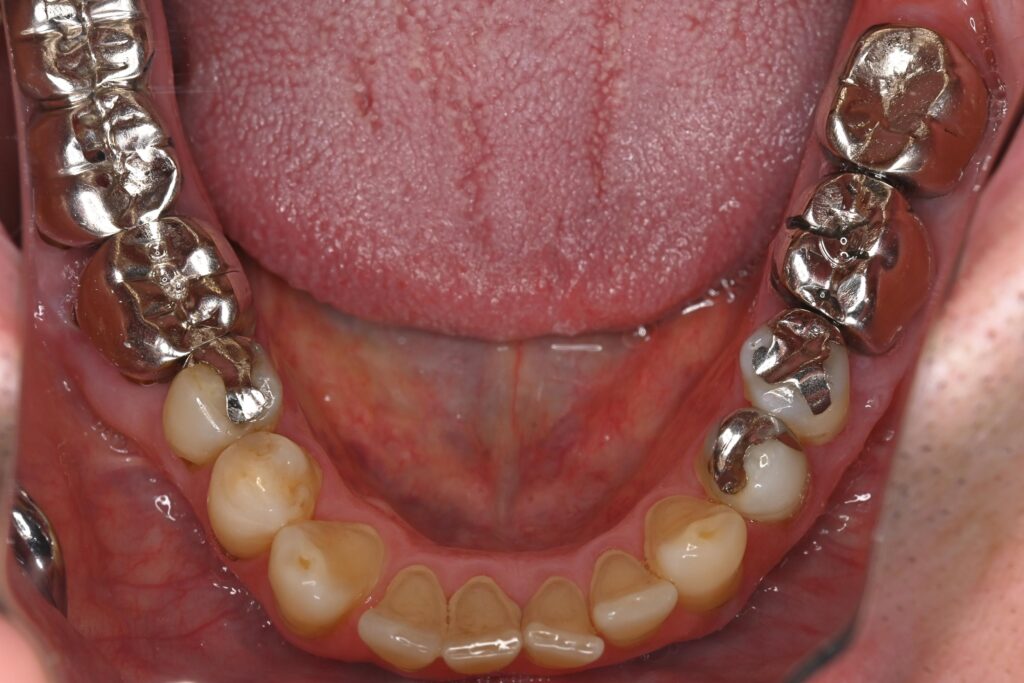

初診時の口腔内の状態:

お口全体に虫歯や歯周病の原因となるプラーク(歯垢)が多く付着していました。右上奥歯は重度の虫歯で歯冠部(歯の頭)が失われており、左下奥歯は過去の治療箇所から細菌が入り込み、根の先に炎症が起きている状態でした。

また、左右の奥歯にはWSD(楔状欠損)があり、知覚過敏も見られました。

Before